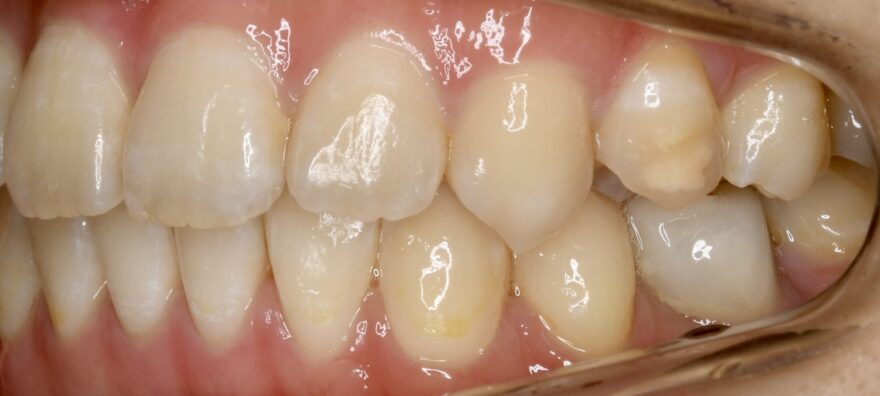

初診時の口腔内写真

上下の歯列の真ん中(正中)が合っていません。

この方向から見ると、前歯が出ていることが分かります。

乳歯の根本が腫れています。

前歯のガタガタが気になります。